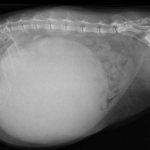

• Злокачественные новообразования (рак). В этом случае опухоли жестче, растут многократно быстрее, иногда их появление отнимает несколько недель. Эта причина образования шишек крайне опасна, т.к. посредством метастазирования опухоли могут быстро разноситься по всему организму.

• Шишки кистозной природы. Обычно кисты (заполненные жидкостью пузыри) появляются во внутренних органах, но бывают и более редкие случаи их образования на лапах или иных поверхностях тела. Растут они довольно медленно, но их появление доставляет животному много неприятностей: они сильно болят, зудят, отчего кот постоянно их чешет или даже разгрызает до крови. К такому процессу часто добавляется участие патогенной гноеродной или некротической микрофлоры.

• Наконец, шишка может развиваться изнутри, т.е. быть следствием наростов на самой кости. Это бывает следствием плохо заросших переломов, или же, что куда хуже, быть признаком сарком, остеобластом и прочих онкологических патологий костной ткани.